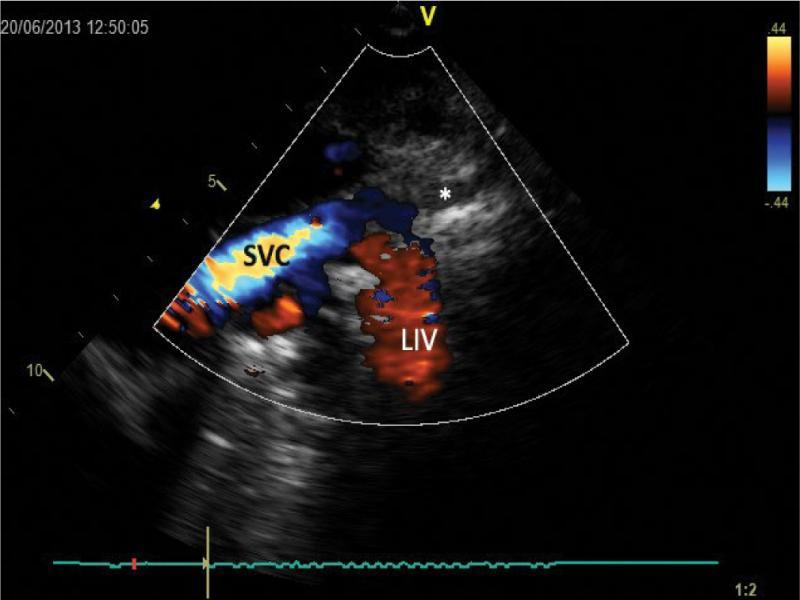

High parasternal view (right) visualizing mediastinal structures in the sagittal plane. Superior vena cava (SVC) with a wide venous vessel (LIV) draining into it slightly above the junction with the right pulmonary artery. It is the typical drainage site of the azygos vein, though in normal conditions it is markedly less intensely color-filled. Another important observation is a significant increase in flow rate in the proximal segment of the superior vena cava. (*) right brachiocephalic vein